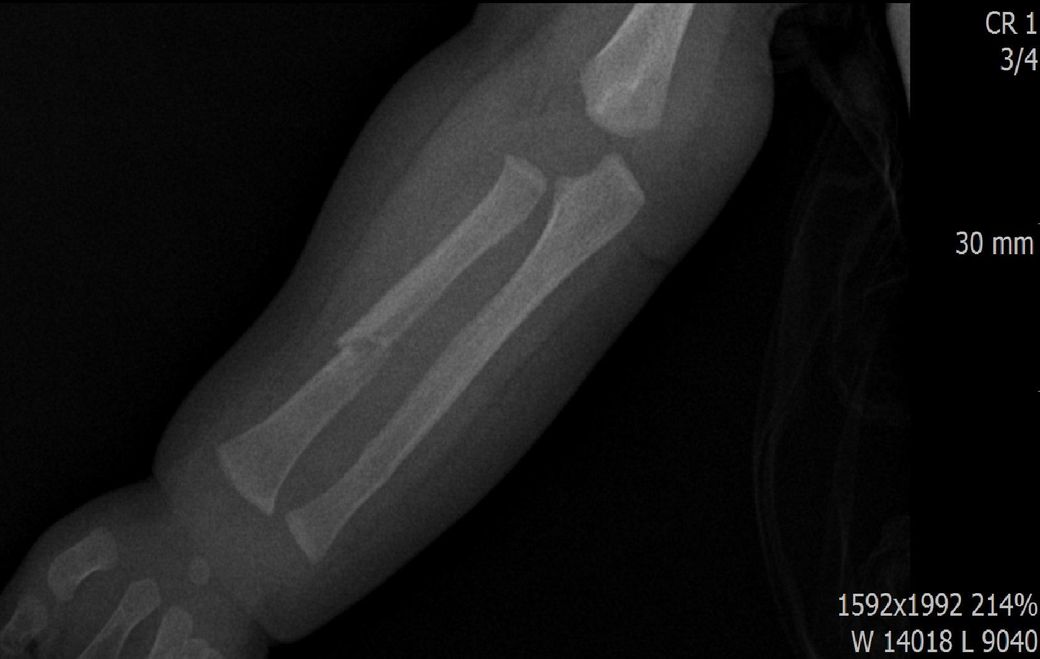

다름이 아니라, 첨부드린 엑스레이(X-ray) 사진처럼 골절 사실을 알게 되고 골절 발생 시점 대략적으로나마 추정시기를 파악하려고 문의 드리게 되었습니다

1) 3월 30일 촬영한 X-ray만으로 정확한 골절 시기를 100% 특정하는 데에는 한계가 있다는 점 충분히 인지하고 있기에 촬영날짜 기준으로 대략적으로 어느정도 시점에서 발생되었을 것으로 추측(ex 당일, 7~10일전, 7~14일 전, 10일 ~ 20일전, 14일 ~ 30일전 등등등)되는지 이해하고 싶습니다.

• 4번 째 사진